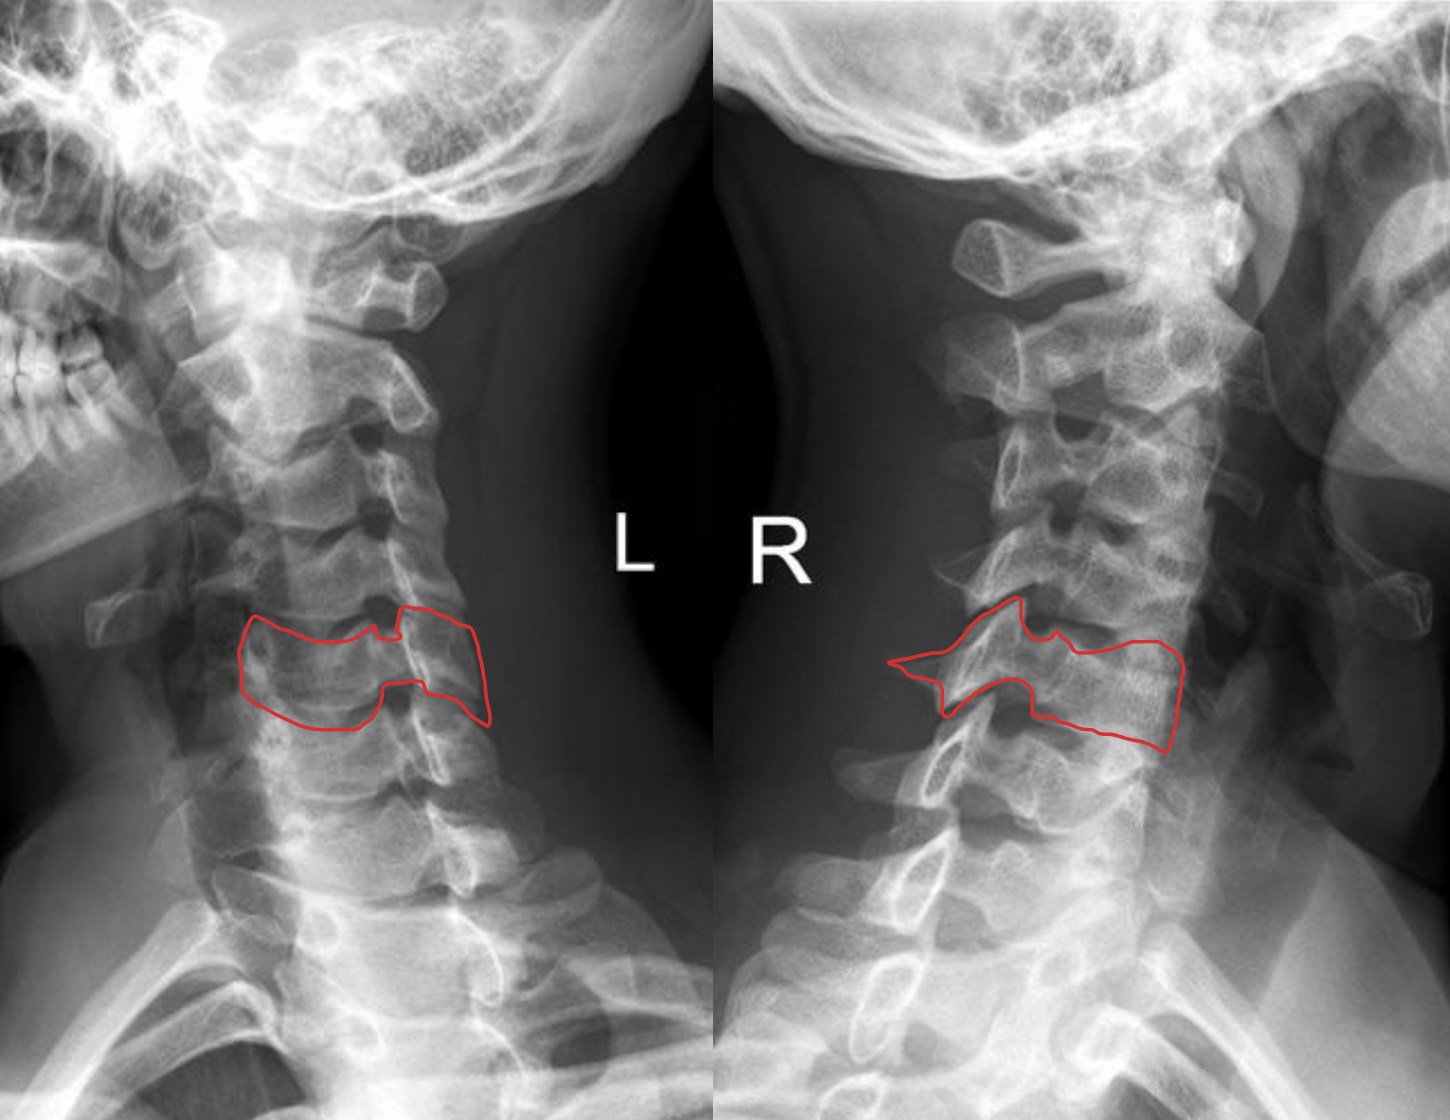

C4